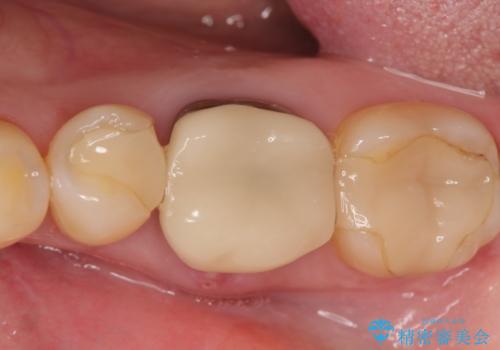

オールセラミッククラウンについて

今回用いたオールセラミッククラウンはジルコニアフレームという白い素材の上にセラミックを盛っているため、審美性が非常に高いのが特徴です。

また、ジルコニアは人工ダイヤモンドの材料にも使われているほど高い強度を持っており、そのためオールセラミッククラウンは審美性だけでなく、奥歯やブリッジの補綴も可能とするクラウンです。